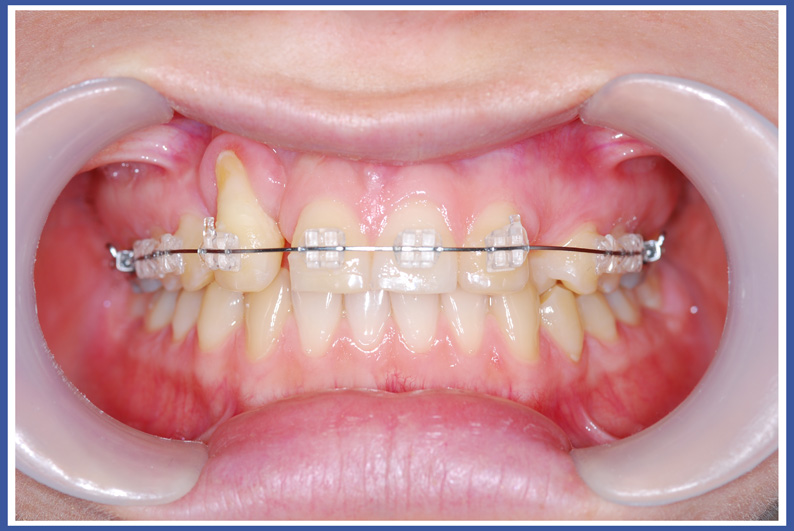

סמכים אורתודונטים (גשר) Brackets:

האמצעי הנפוץ ביותר כיום להזזת שיניים. הסמכים המודבקים לשיניים והחוט שעובר ביניהם מאפשרים להזיז את השיניים בכל שלושת המימדים בשליטה מלאה על התנועה, בניגוד לפלטות שיכולות להזיז שיניים רק בהטיה (רק לשנות את הזווית של השן בלסת). סמכים יכולים להיות מתכתיים או שקופים.

לסמכים המודבקים לשיניים יש יתרונות רבים אך יש להם גם חסרונות. החסרון העיקרי הוא הצטברות שאריות מזון וחיידקים עליהם. כדי למנוע סכנה לעששת (חורים) מסביב לסמכים, יש להקפיד על צחצוח שיניים קפדני במהלך הטיפול, ולהמנע ככל האפשר ממזון המזרז את התפתחות העששת (מזון עשיר בסוכר).